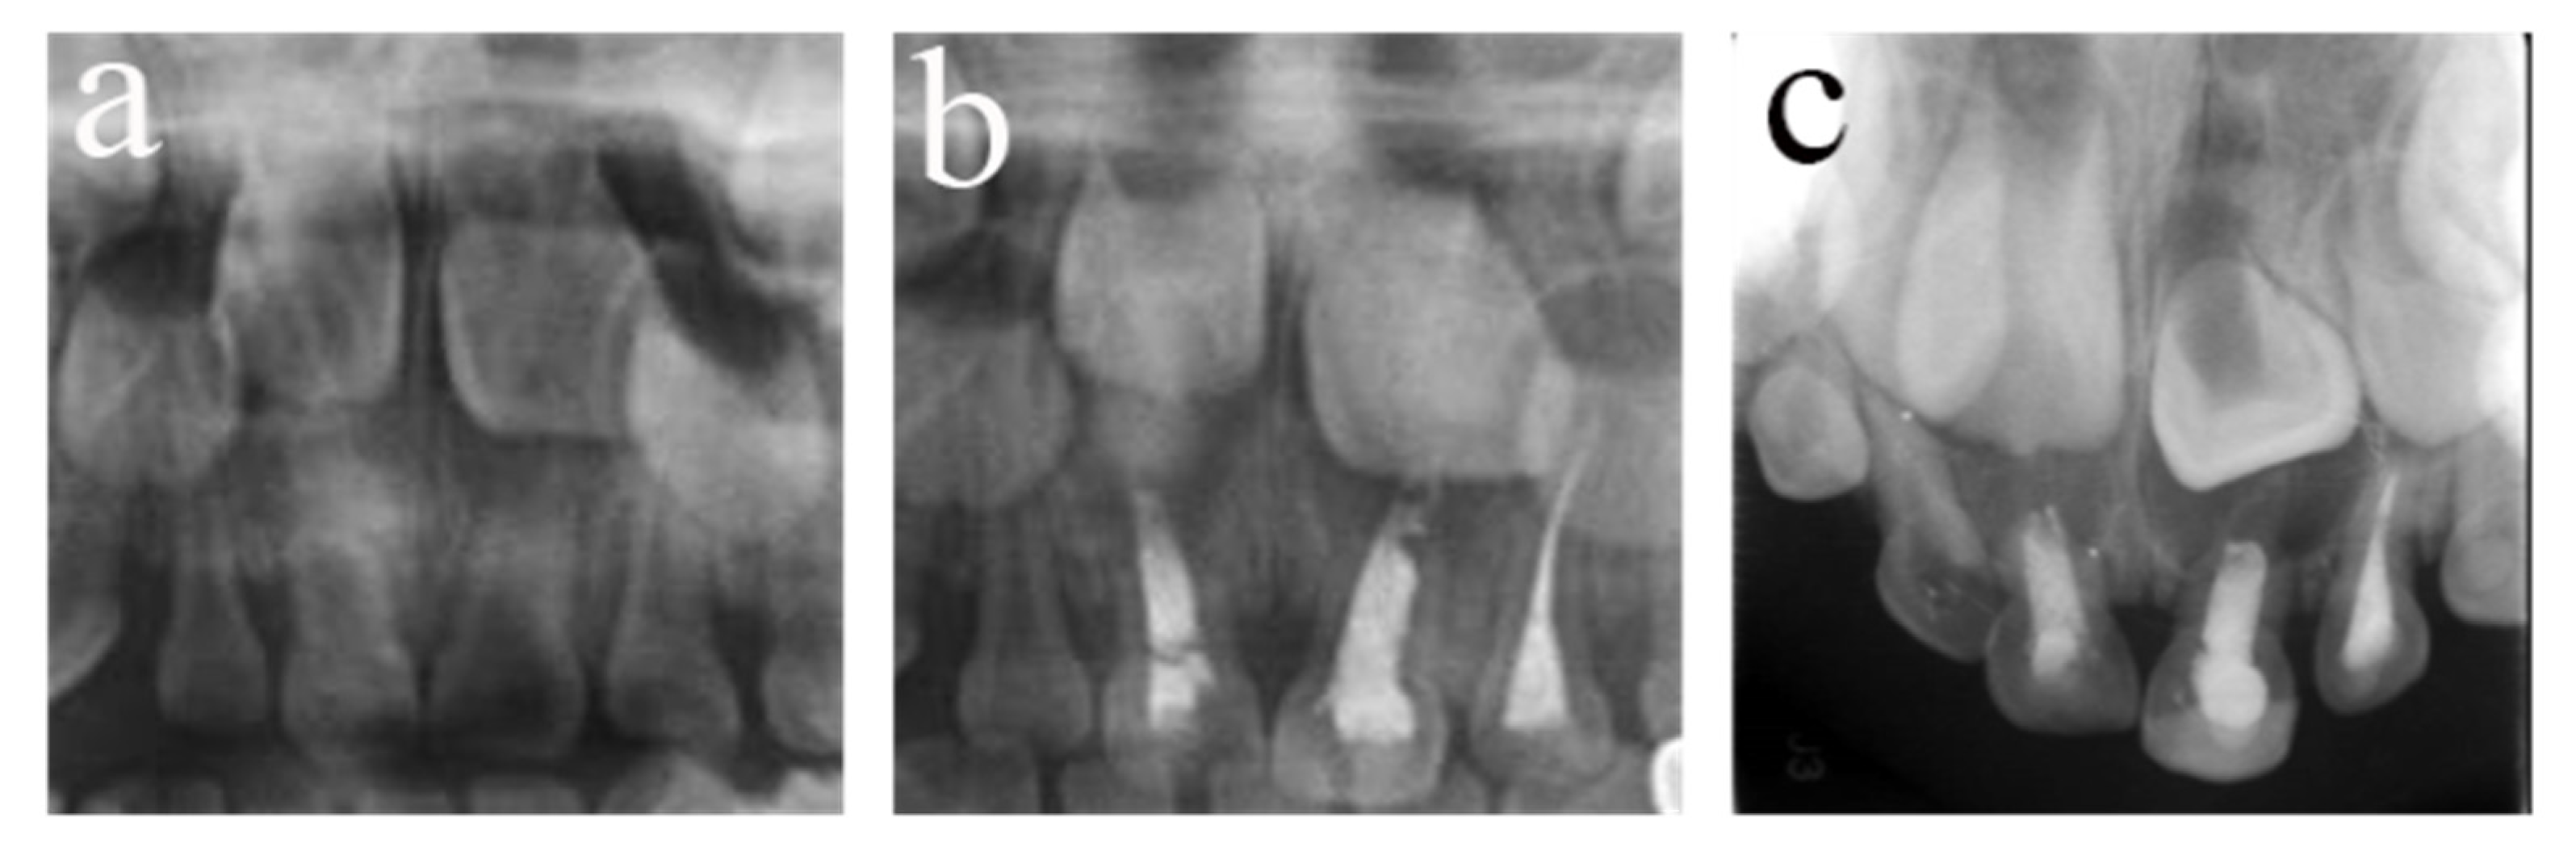

Figure 6.

#64 received pulpectomies under DGA with a 32-month follow-up period (63-month-old male child). (a) The preoperative radiograph revealed nothing abnormal in the periapical area. (b) Radiograph taken one week postoperatively showing optimal filling. (c) Thirty-two months after the operation, #64 was lost early, and #24 erupted prematurely. Pulpectomies in #64 failed.